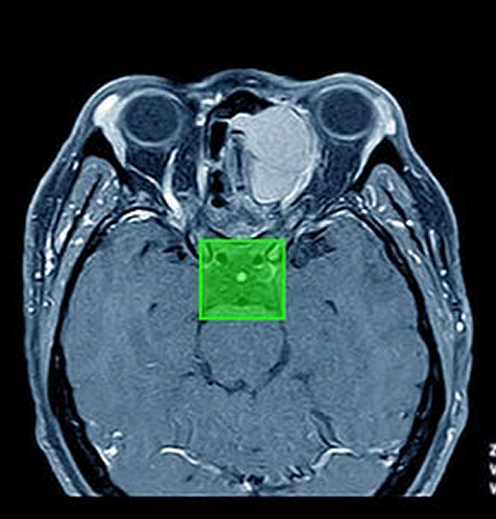

Medical Data Annotation is the meticulous process of labeling and tagging medical images to provide structured data for training AI algorithms. Whether it’s a CT scan, MRI, or X-ray, each pixel or region must be annotated by skilled professionals to train AI to detect anomalies with high precision.

Neurology: Annotations in brain MRIs help identify conditions such as Alzheimer’s, epilepsy, and multiple sclerosis.